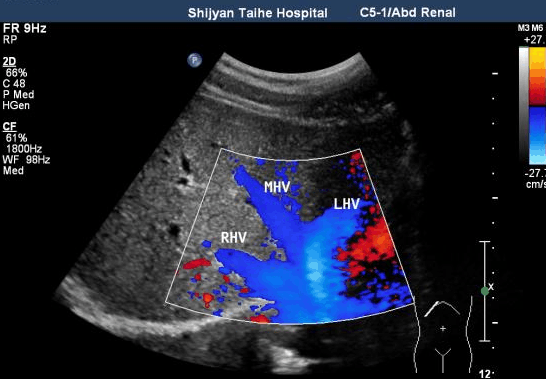

肝癌:甲胎蛋白(AFP)+肝脏超声(B超)

查肝癌需要做“甲胎蛋白+肝脏超声”联合检查。甲胎蛋白是一种肿瘤标志物,可以通过采集静脉血进行检测。该指标出生一年后维持低水平,只有患肝病时才会升高,是临床诊断原发性肝癌的常规指标之一。

需要注意的是,单独用甲胎蛋白普查,会有一定漏诊率,因为只有80%左右的肝癌患者甲胎蛋白会升高,也就是说单纯的检测血清甲胎蛋白值正常,仍不能完全排除患肝癌的可能性。多年的临床经验证明,肝脏超声联合血清甲胎蛋白检测肝癌的准确率达到90%以上,是临床诊断早期肝癌首选的检查方法。

肝脏超声检查